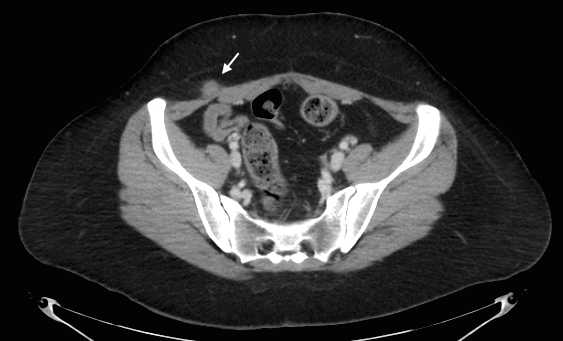

We present the case of a 28-year-old woman with a personal history of cesarean delivery 7 years ago who consulted due to pain relating to a mass in her right lateral abdominal wall. Physical examination showed a 2 cm nodular mass at the right lower quadrant, 10 cm away from the Pfannenstiel scar. Palpation was painful and no protrusion was felt after Valsalva or during bipedestation. Ultrasound and CT scan showed a 17 mm nodular mass at the union of oblique muscles and rectus abdominis muscle. With these findings we performed surgery to remove the mass and the specimen analysis confirmed endometrioma.